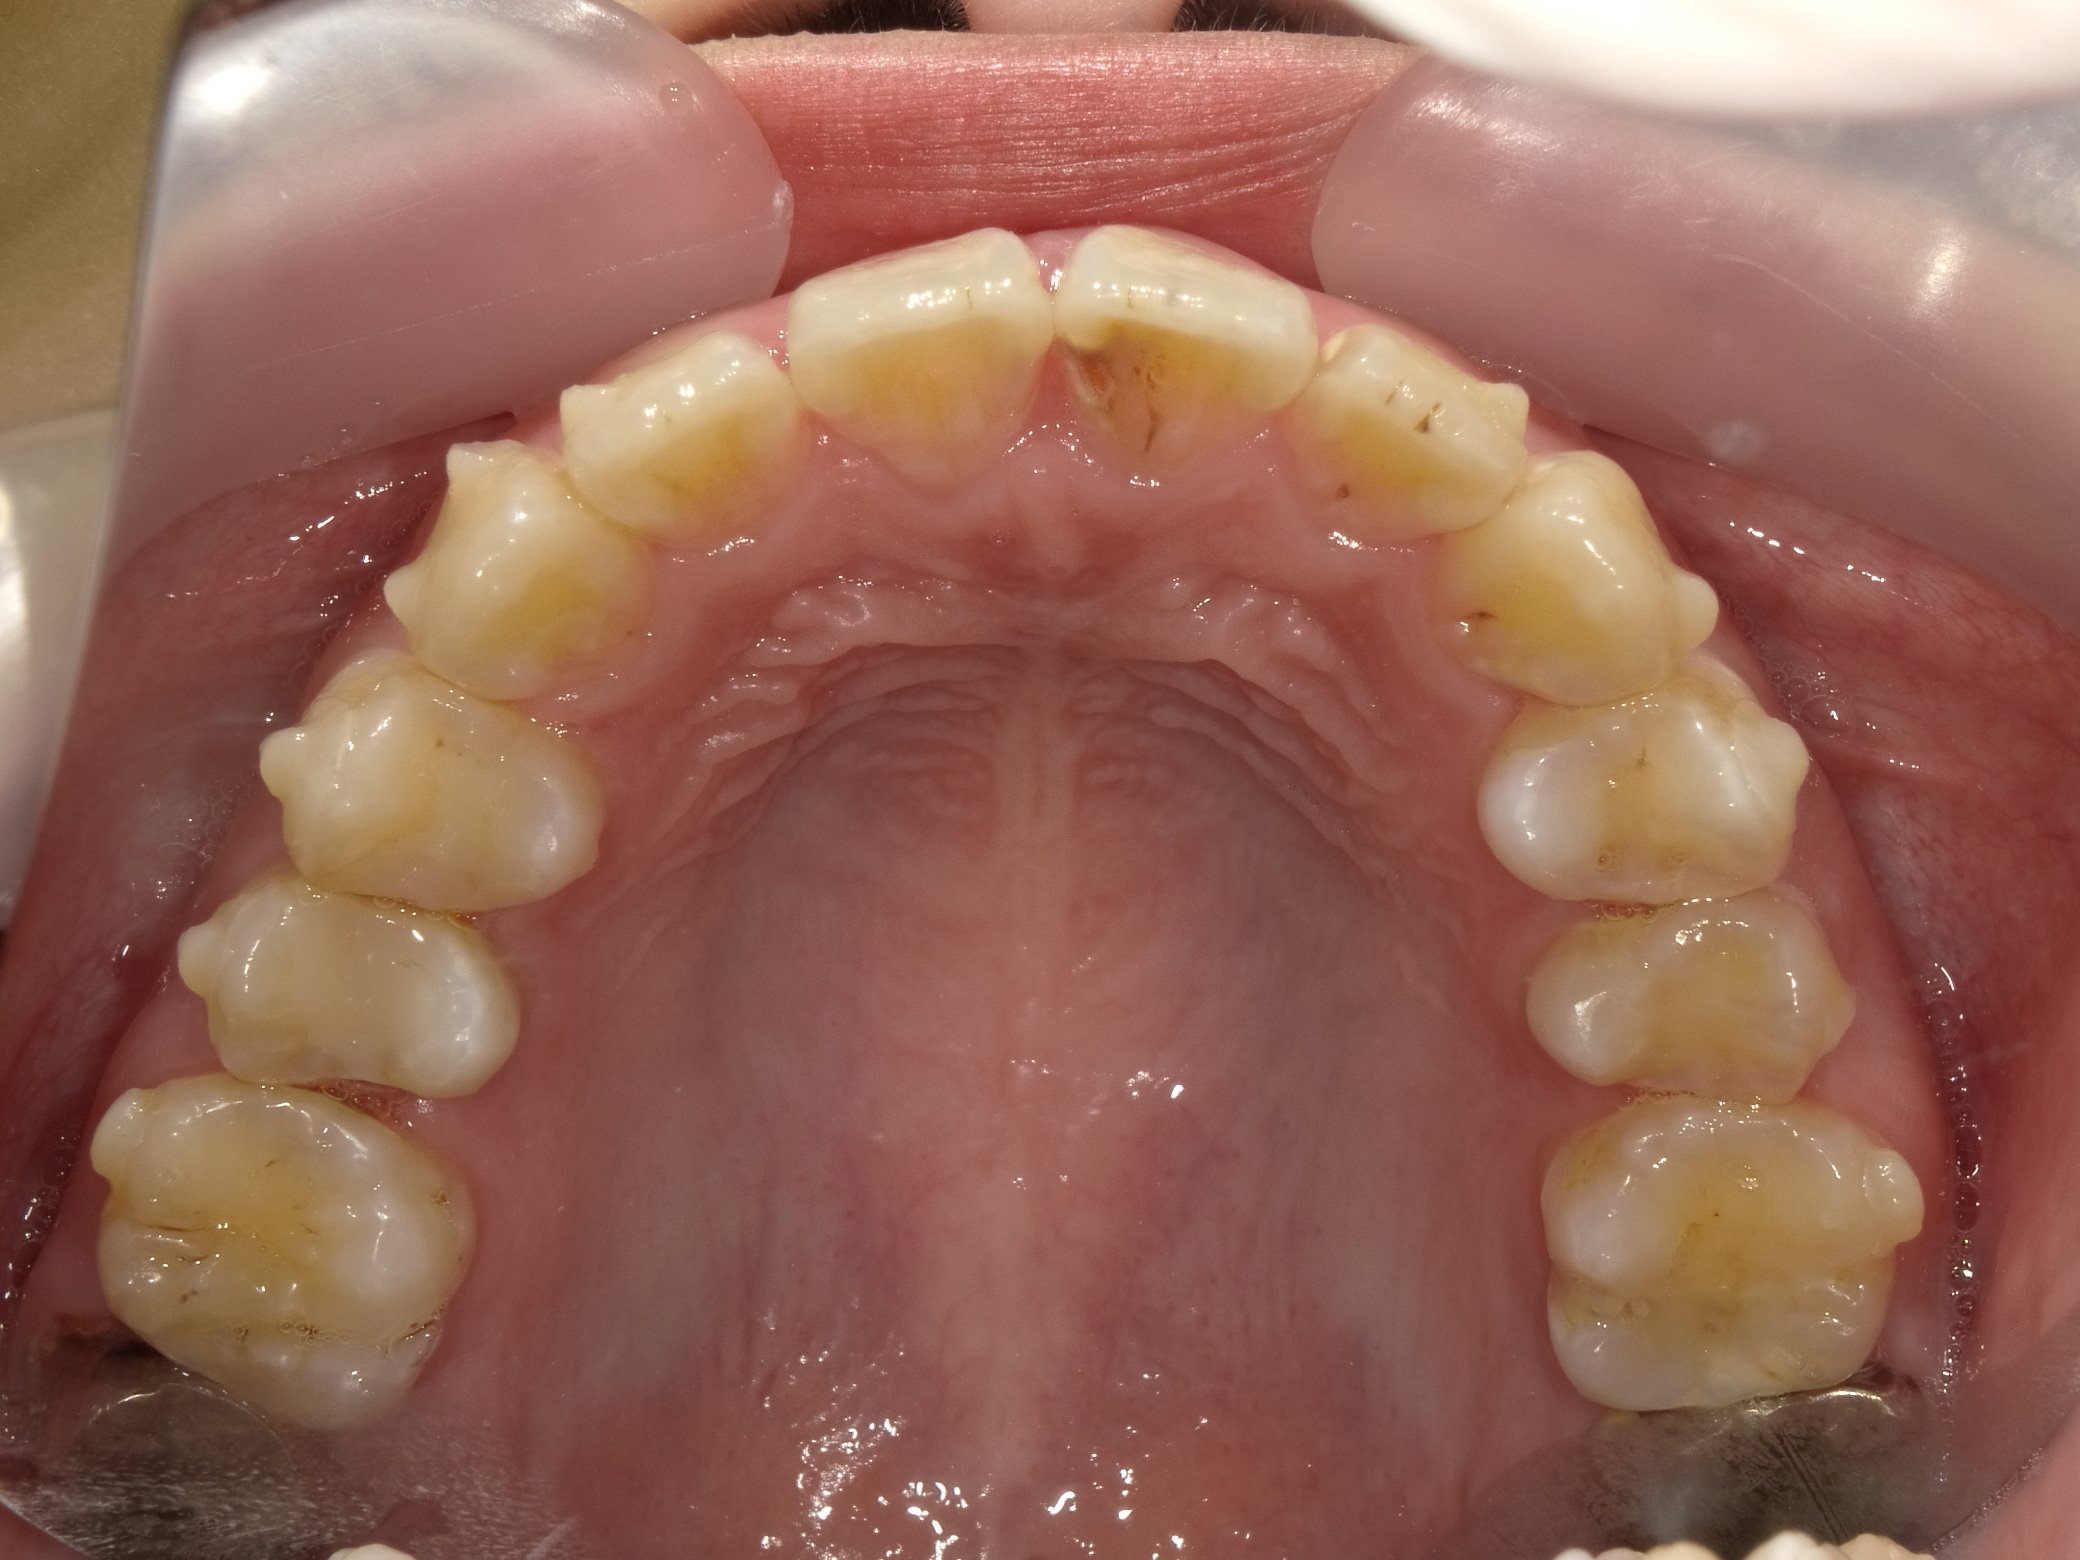

■ 治療後の状態(After)

インビザライン矯正により前歯の傾きが改善され、歯列のアーチが整ったことで出っ歯の印象が軽減しました。

また、下顎の歯の重なりも解消され、歯並び全体がすっきりと整った状態になっています。

■ 治療内容の概要

治療方法:マウスピース型矯正装置(インビザライン)

治療期間:6ヶ月